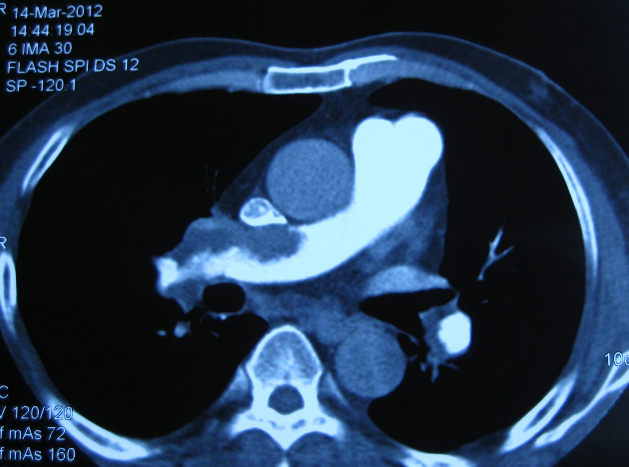

6.CT肺動脈造影

CT可直觀判斷肺動脈栓塞的程度和形態(tài),以及累及的部位及范圍,是診斷PE的重要無創(chuàng)檢查技術,但其對亞段及以遠肺動脈內(nèi)血栓的敏感性較差。